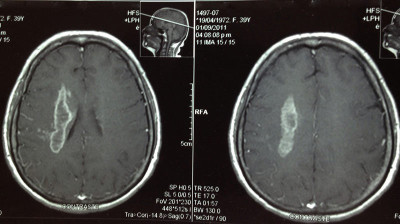

Casos Neuroloquirúrgicos

Envíado por Dr. Ruben Eduardo Amaya Contreras